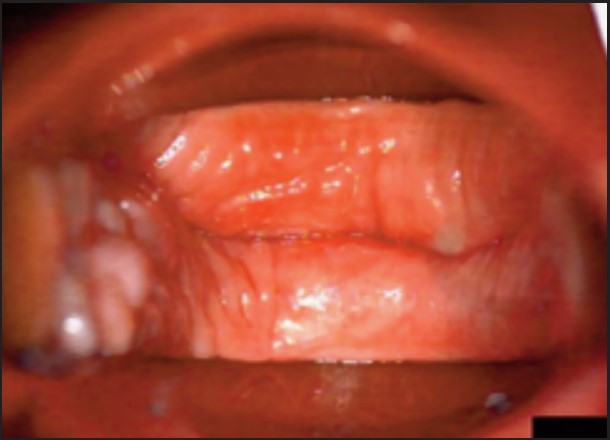

Під час спостереження до та після процедури, через 16 і 36 діб було зроблено вагінальні фотографії за допомогою Tele-Cervico (цервікографія) та виконано порівняння результатів до /після.

У пацієнток 1, 2 і 3 вагінальні складки утворилися та увиразнилися помітніше та сильніше, ніж вони були до лікування, ми оцінили цей клінічний результат після 1-го сеансу (через 16 діб). На нашу думку, такі виразні складки свідчать про підтяжку слизової оболонки піхви, що добре впливає на ущільнення піхви та проблему нетримання сечі. Через 36 діб після процедури ми спостерігали, що зруйнована анатомічна структура піхви відновила Н-подібну форму, тобто стала набагато здоровішою. Зокрема, у пацієнтки 4 структура піхви була цілковито зруйнована, стінки піхви обвисали через втрату еластичності. Однак через 36 днів після процедури структура піхви повністю відновила здорову Н-подібну форму [Див. Малюнок 3].

Пацієнтка №1

До

Після 36 діб